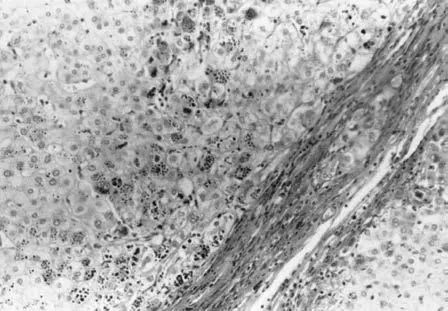

随后,超声指导下的肝活检发现肝结节和纤维化,提示肝硬化伴脂肪变性和部分胆汁淤积,但未发现气球样变和小叶炎症。过碘酸-希夫(PAS)阳性的肝细胞球形小体增多,符合纯合子PIZZ α1-抗胰蛋白酶(AAT)缺乏的典型组织学特征(图1)。

图1 纯合子PIZZ AAT缺乏有独特组织学特征。图中显示了肝细胞中的过碘酸-希夫(PAS)阳性、淀粉酶抵抗的球形小体

虽然不是强制性的,但对一些AATD患者可以使用肝活检技术确诊;比如本文所介绍的这例病例,在可能存在其他疾病的情况下,为避免混淆诊断,便采用了活检手段。在AATD患者的肝活检切片中,通常可见由错误折叠的AAT蛋白形成的细胞内碘酸-希夫(PAS)阳性球形小体(图1)。